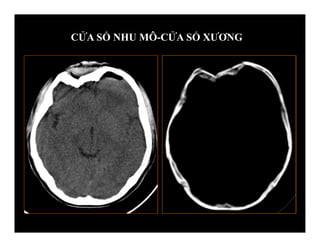

-Khảo sát không cản quang (CTSN cấp)

-Khảo sát có cản quang (mãn, biến chứng)

-Cắt liên tục/ Độ dày lát cắt: khoảng cách lát

cắt 10/10 mm hay 5/5 mm.

-Cửa sổ nhu mô- cửa sổ xương

KHẢO SÁT CT TRONG CHẤN THƯƠNG

SỌ NÃO

CỬA SỔ NHU MÔ-CỬA SỔ XƯƠNG